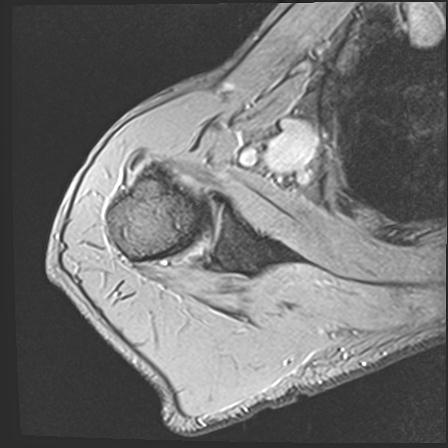

60058 3/9 11/4 右肩 2R+MRI 73歳男性 肩腱板損傷